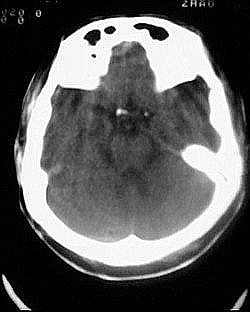

患者/49y/ 女/4年前有脑梗, 现因右侧肢体无力来院做ct扫描 ! 老师们看看这骨头有事吗?钙化点是什么原因呀??

1.颅骨对称性、形态规整性增厚,应属发育异常。四叠体池左后侧单发点状钙化,无其他阳性表现,多属正常,不需要过多关注。

2.双侧基底节区域多发性梗塞灶。

2.颅骨内外板广泛性增厚,板障狭窄甚至消失,双侧对称。无明显相应临床症状。考虑“泛发性骨皮质增厚症”。可进一步检查下颌骨及管状骨骨干。(下颌骨骨小梁增多、密集,密度增高亦为本病特点,管状骨骨干皮质向内增厚引起骨皮质厚度增加,骨密度增浓、髓腔狭窄但不消失,骨干周径较少增加)。与石骨症鉴别,后者很少影响颅盖骨和下颌骨,管状骨改变主要累及干骺端和骨骺,而骨干皮质较少增厚,椎体和髂骨翼有特征性表现。

“泛发性骨皮质增厚症,又称骨内膜增生症(endosteal hyperostosis):分为常染色体隐性遗传性疾病(van buchem)和常染色体显性遗传性骨硬化症(worth病)。后者更少见,亦较轻。两者的病理上均为骨内膜 成熟的板状新生骨形成,髓腔变窄。颅骨、颅底骨 、下颌骨,肋骨、四肢骨及骨盆骨、脊柱均可见骨内膜增生,髓腔变窄或消失,但骨外径不加大,骨骺不累及。”